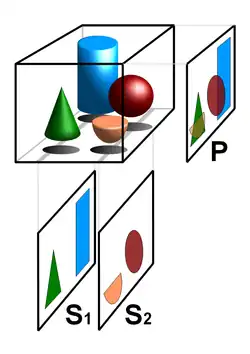

Ein Schnittbild gibt die inneren Strukturen so wieder, wie sie nach dem Aufschneiden des Objekts oder nach dem Herausschneiden einer dünnen Scheibe vorlägen. Man spricht hier von einer überlagerungsfreien Darstellung der entsprechenden Objektschicht – im Unterschied zu Projektionsverfahren wie etwa der gewöhnlichen Röntgenuntersuchung, bei der sich alle Strukturen überlagern, die im Strahlengang hintereinander liegen. Dieser Unterschied wird in der nebenstehenden Abbildung mit zwei tomografischen Schnittbildern (S1 und S2) und einem Projektionsbild (P) des gleichen Volumens illustriert.